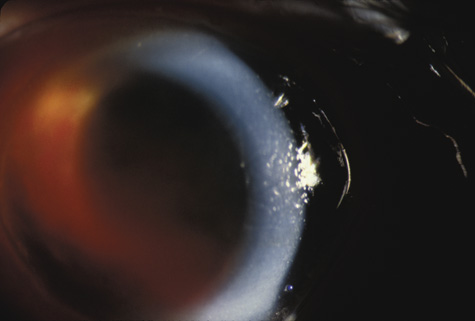

LENS

When the lens is struck by the cornea or by a strong shock wave, a transient anterior subcapsular cataract, known as a rosette cataract, may develop (Fig. 6). Repeated trauma, as in boxers, often causes posterior subcapsular cataract. Blunt trauma can also result in rupture of the anterior or posterior capsule.44,45 In severe cases, iridodonesis or a bead of vitreous in the anterior chamber signals a subluxed lens. Dislocation may also occur (Fig. 7). It is important to remember that ocular trauma is common, but lens dislocation is rare. Therefore, in patients with a dislocated lens, the clinician should always rule out predisposing causes such as Marfan's syndrome, homocystinuria and syphilis. In rare cases the lens itself can rupture and cause phacolytic glaucoma.

Fig. 6. An anterior subcapsular rosette cataract.